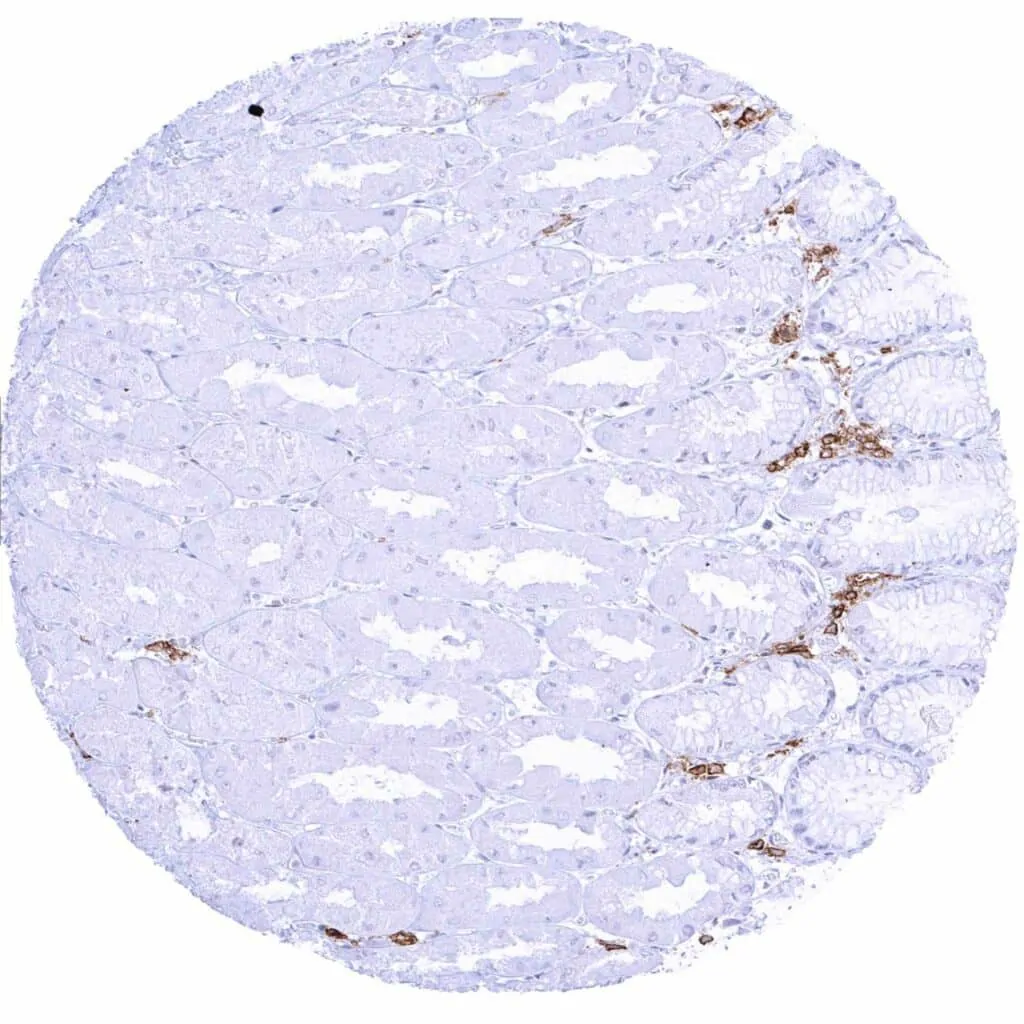

Lymph node – Distinct CD38 staining of a subset of lympho–monocytic cells.

Lymph node – Distinct CD38 staining of a subset of lympho–monocytic cells